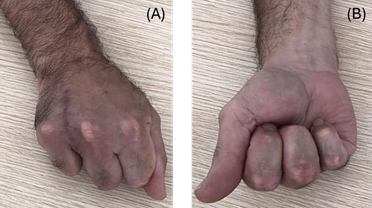

The worker resumed professional activity 14 weeks after the surgery (Figure 4). In the occupational health examination, it was verified that he maintained some pain in the scar region. However, full recovery of hand joint mobility was observed, with no significant differences in grip strength between his hands. Hence, a conditional fitness was issued in order to provide a gradual increase in both workload and demand, for the first 60 days of readaptation to the job and limited frequent gripping movements with the right hand in line with the symptoms.

Figure 4: (A, B) Photographs of the grip after recovering from the surgery.

After this time, he was re-evaluated having reported that the pain had vanished, and on physical examination, no abnormalities were observed. After interdisciplinary discussion the patient was deemed fit with re-evaluations of the work fitness every 6 months.